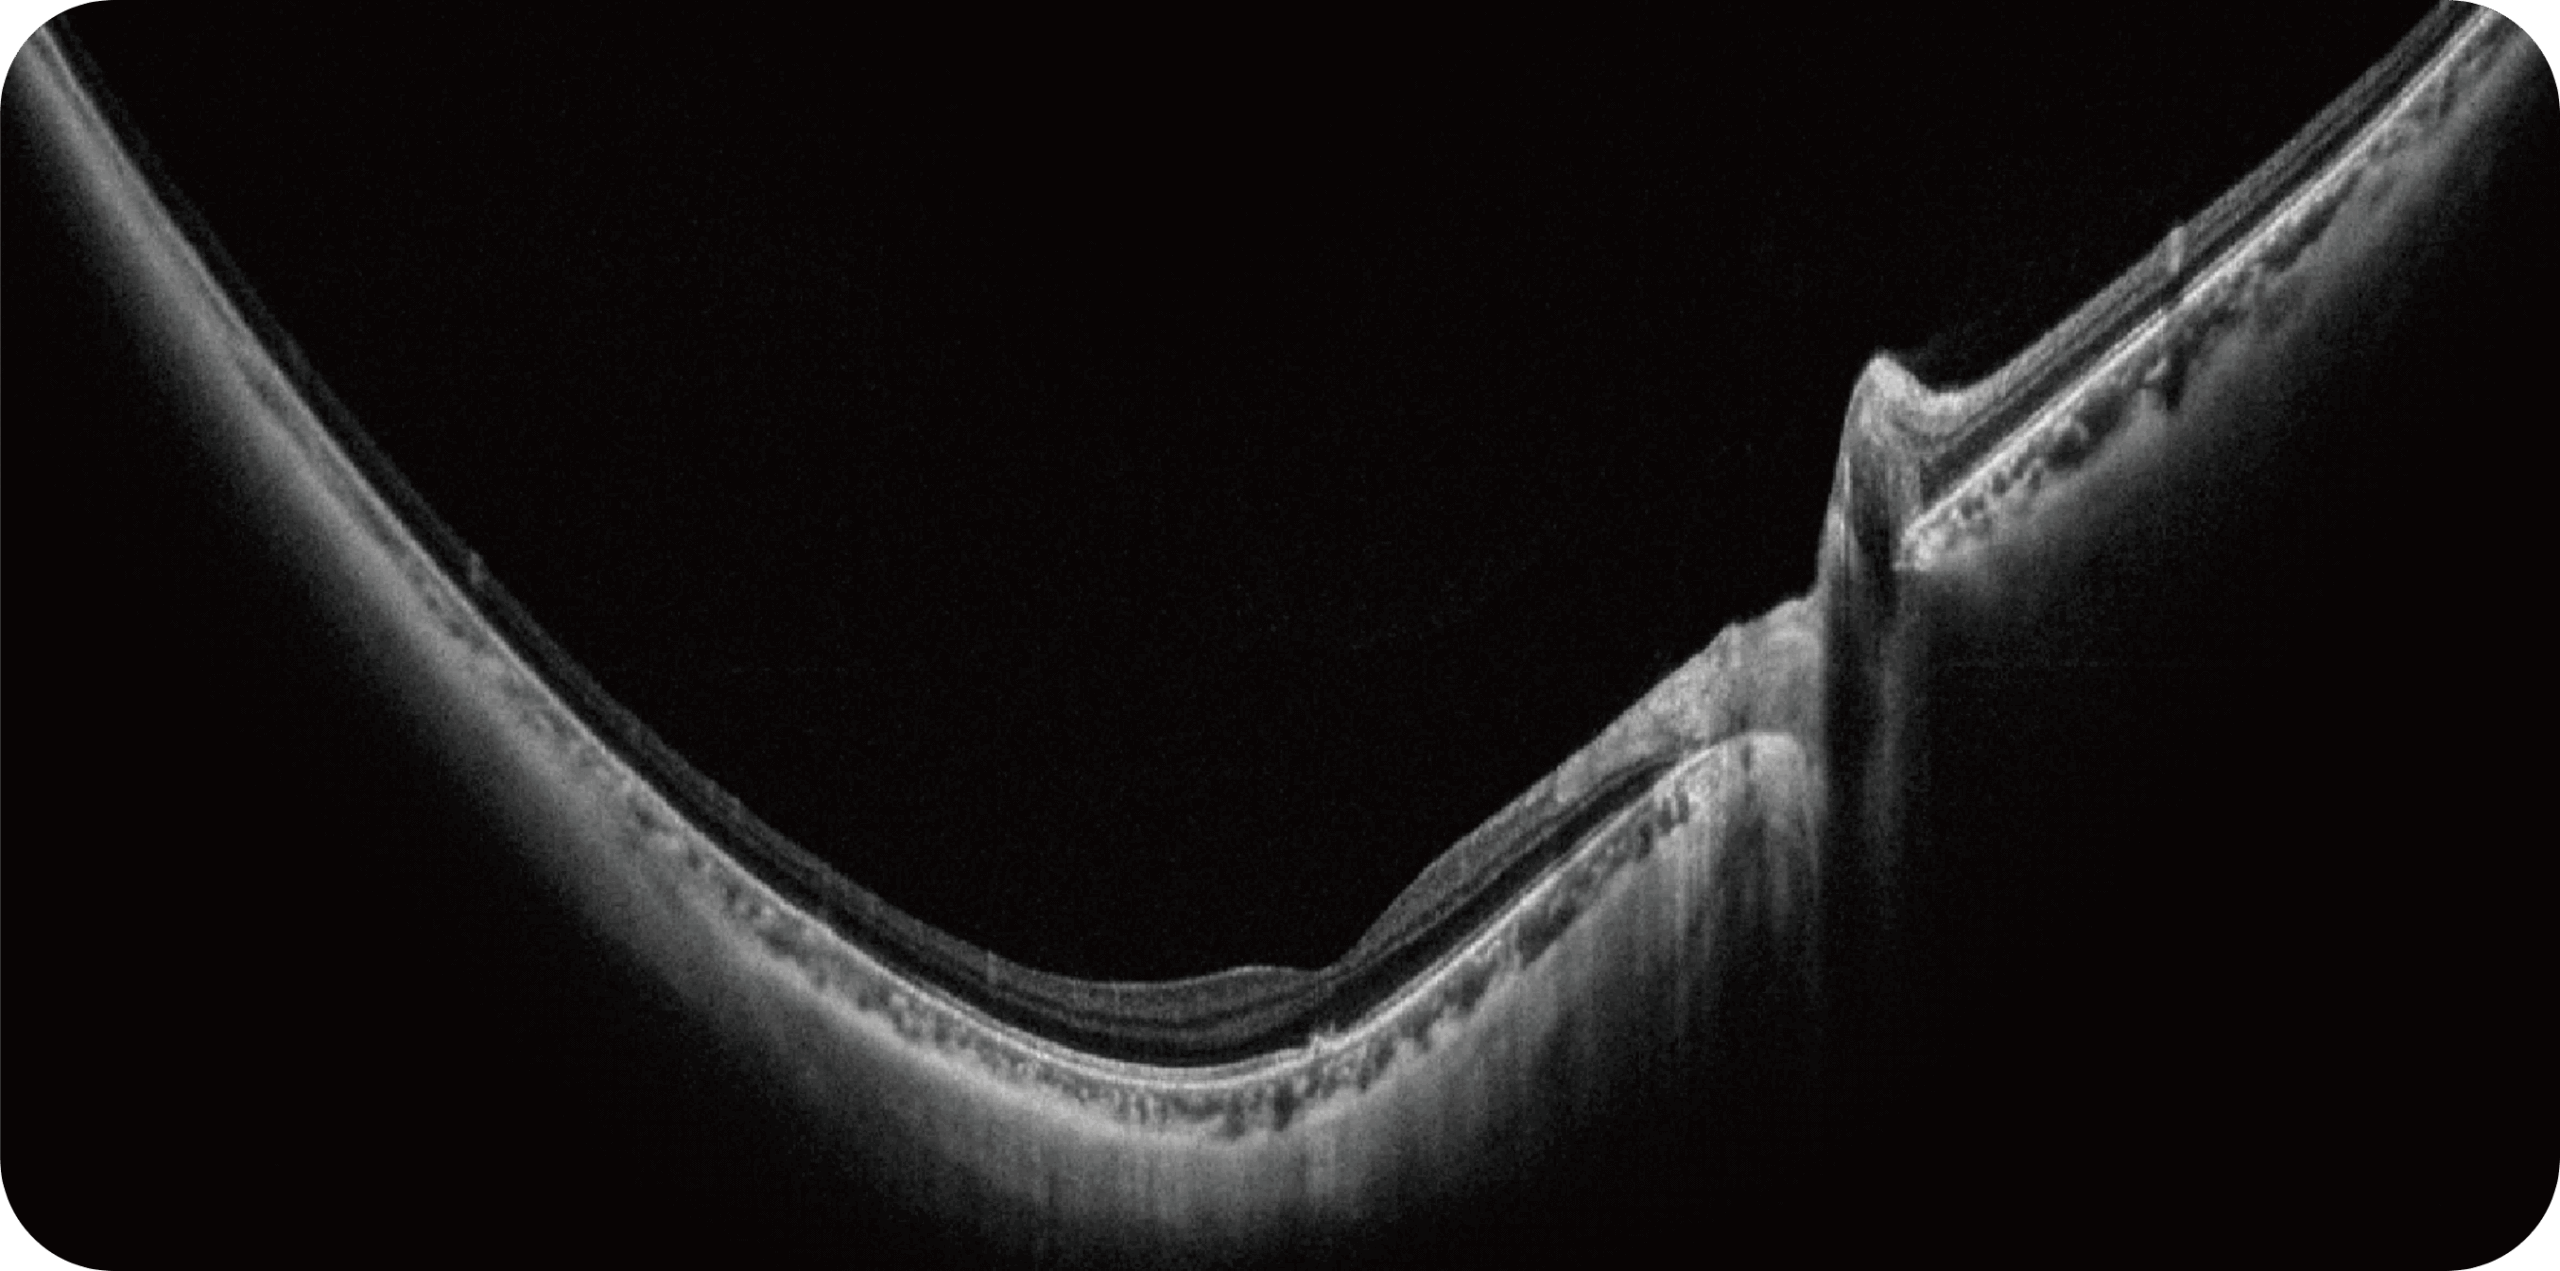

Uma única varredura pode obter rapidamente imagens sincronizadas de imagens coloridas de campo ultralargo/FAF/FFA/ICGA e SS-OCT, alcançando sincronização em tempo real e alinhamento preciso de imagens planas e estruturais da retina, melhorando significativamente a eficiência da inspeção e otimizando o processo de diagnóstico e tratamento.” Uma única varredura pode obter rapidamente imagens sincronizadas de imagens coloridas de campo ultralargo/FAF/FFA/ICGA e SS-OCT, alcançando sincronização em tempo real e alinhamento preciso de imagens planas e estruturais da retina, melhorando significativamente a eficiência da inspeção e otimizando o processo de diagnóstico e tratamento.

Altamente integrado com tecnologias como SLO confocal e SS-OCT, ele combina imagens coloridas SLO de campo ultralargo, angiografia confocal a laser, autofluorescência e imagens tomográficas de segmento anterior e posterior ultraamplas e profundas em um único sistema.

Retinopatia diabética, degeneração macular e outras doenças da retina.

Estudo da coroide em casos complexos.